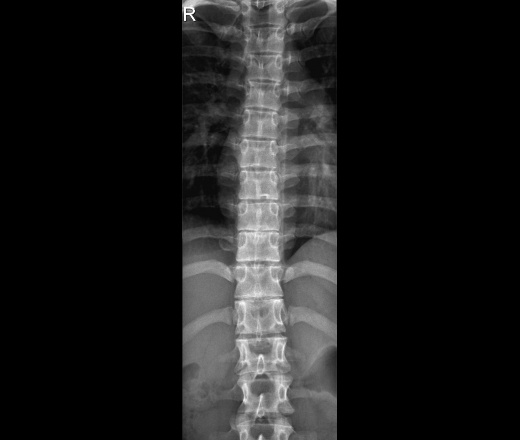

Уважаемые коллеги, помогите разобраться с рентгенологической картиной.

Девочка, 17 лет, жалобы на периодические боли в спине при сидении, утомляемость. Изменения в осанке родители отмечают в течении года. Жалобы на боли в спине в течении последних трех месяцев, постепенно становятся чаще. Интенсивность не высокая, ноющий характер, купируются после смены положения тела, массажа. Травму отрицают. Не спортсменка.

Клинически есть изменения в осанке, но пальпаторно болезненность не выявлено, движения не ограничены, безболезнены.

Смущает не соответствие клинической и рентгенолоогической картины, локальные изменения.

Подскажите, в каком русле думать, что за изменения могут быть. Или это просто локальный остеохондроз?

Предположу болезнь Шейермана-Мау

Нет характерной кифотизации. Сами позвонки тоже не клиновидные. Атипичная форма?

Кифотизации действительно нет. Но некоторые позвонки клиновидной формы есть.

Еще есть S-образное искривление позвоночного столба

Спасибо. Сколиотическую деформацию описали. Смущали локальные изменения и невыраженная клиновидная деформация позвонков при выраженном снижении высоты дисков, бледная клиническая картина.

Не атипичная. Для этой болезни типичны две локализации: позвонки на высоте грудного кифоза и Th10-L2. Когда изменения на уровне кифоза, то он усиливается. А если второй вариант, то кифотизации, само собой, не будет. Поэтому синоним "юношеский кифоз", как по мне, не совсем полноценный, потому как есть привязка строго к среднегрудному отделу. Но у этой болезни есть и другие синонимы: спондилодисплазия, остеохондропатия апофизов тел позвонков и т.д., что дает о ней более полное представление.

сделать бы томогрпммы. Возможно и конкресценция выскочит.